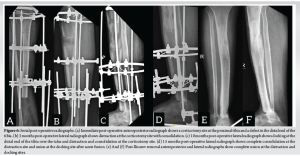

A 36-year-old male presented after noticing a gradually increasing swelling over his right ankle for the past 3 months. It was associated with a dull and diffuse type of pain which was aggravated with weight bearing. He denied a history of any previous trauma. He had noticed significant weight loss in the past 6 months. On clinical examination, there was a localized swelling of size 5 × 3 cm over the medial aspect of the ankle, which was tender, immobile, with ill-defined edges, and was bony hard in consistency. The range of movements in the ankle was minimally restricted in comparison with the contralateral side. There was no neurovascular deficit in the affected limb. Plain radiographs of the affected limb were done and showed an ill-defined, radiolucent, expansile lesion in the medial aspect of the distal end of the tibia, with a posteromedial cortical breach and a narrow zone of transition (Fig. 1a and b). Magnetic resonance imaging of the affected limb was performed and showed a T1 hypointense lesion of size 6.1 × 4.7 × 7.3 cm in the epi-metaphyseal region of the distal tibia (Fig. 2a), with multiple cystic areas and fluid levels (Fig. 2b) – suggestive of giant cell tumor of the distal tibia with secondary aneurysmal bone cyst formation. Biopsy was performed from the lesion, under ultrasound guidance, and showed osteoclast-like giant cells and neoplastic cells with ill-defined borders and eosinophilic cytoplasm, suggestive of giant cell tumor. Based on the radiographic appearance, the tumor was classified according to the Campanacci grading as Type III owing to the presence of ill-defined margins and a cortical breakthrough. After a thorough review of the literature and a multidisciplinary discussion with the surgical oncology team in assessing all the possible options of intervention, pre-operative planning was done, and the patient underwent wide excision of the tumor and was planned for bone transport with an Ilizarov ring fixator (Fig. 3a and b). The patient was positioned supine on the operating table with a primary surgeon on the right side and an image intensifier on the contralateral side. The skin incision was made over the posteromedial aspect, extending from the distal third of the leg to mid-foot (Fig. 4a). The flap was raised posteriorly (Fig. 4b), posterior compartment was dissected, and the great saphenous vein was isolated along its course. Tumor margins were identified, and tibia was osteotomized, giving a 3 cm clearance proximal to the tumor (Fig. 4c). Ligaments around the ankle were cut, and the distal end of the tumor was visualized. The tumor, along with the encased tibialis posterior, was removed in toto (Fig. 4d) and was sent for histopathological examination. A thorough wash was given, and the wound was closed. Three equidistant Ilizarov rings were fixed around the tibia proximal to the osteotomy site using tensioned wires and were interconnected with threaded rods. A half ring was fixed around the midfoot with tensioned wires and connected to the proximal rings (Fig. 5). Proximal tibial corticotomy was done at a level between the proximal and middle rings. Postoperatively, distraction was started from day 7, at the rate of 1mm/day, and was continued for a period of 90 days, resulting in a distraction of 90 mm at the corticotomy site, thereby filling the defect in the distal tibia. Serial radiographs were done to look for consolidation of the regenerate at distraction site and docking of the stump over the talus (Fig. 6a-c). 90 days later, once docking was complete (Fig. 6d), distraction was stopped, and the frame was retained for a period of 180 days, allowing for consolidation of regenerate at the distraction site. Once clinical and radiological signs of union were confirmed at the distraction site, acute docking was performed, and fusion at the ankle was done. The Ilizarov frame was then retained for a period of 6 months. After 6 months, once complete union was noticed at the docking site, the frame was (Fig. 6e and f). The patient was then gradually made to weight bear partially with a walker frame for a period of 4 weeks. Later he was allowed full weight-bearing walking, initially with a walker frame for 2 weeks, followed by an elbow crutch for 2 weeks and unassisted subsequently. He was last followed up 2½ years postoperatively and showed no clinical or radiological signs of recurrence. He was able to walk unassisted with a plantigrade foot. Dorsiflexion and plantarflexion at the ankle were not possible. Minimal passive inversion and eversion movements at the subtalar joint were preserved.